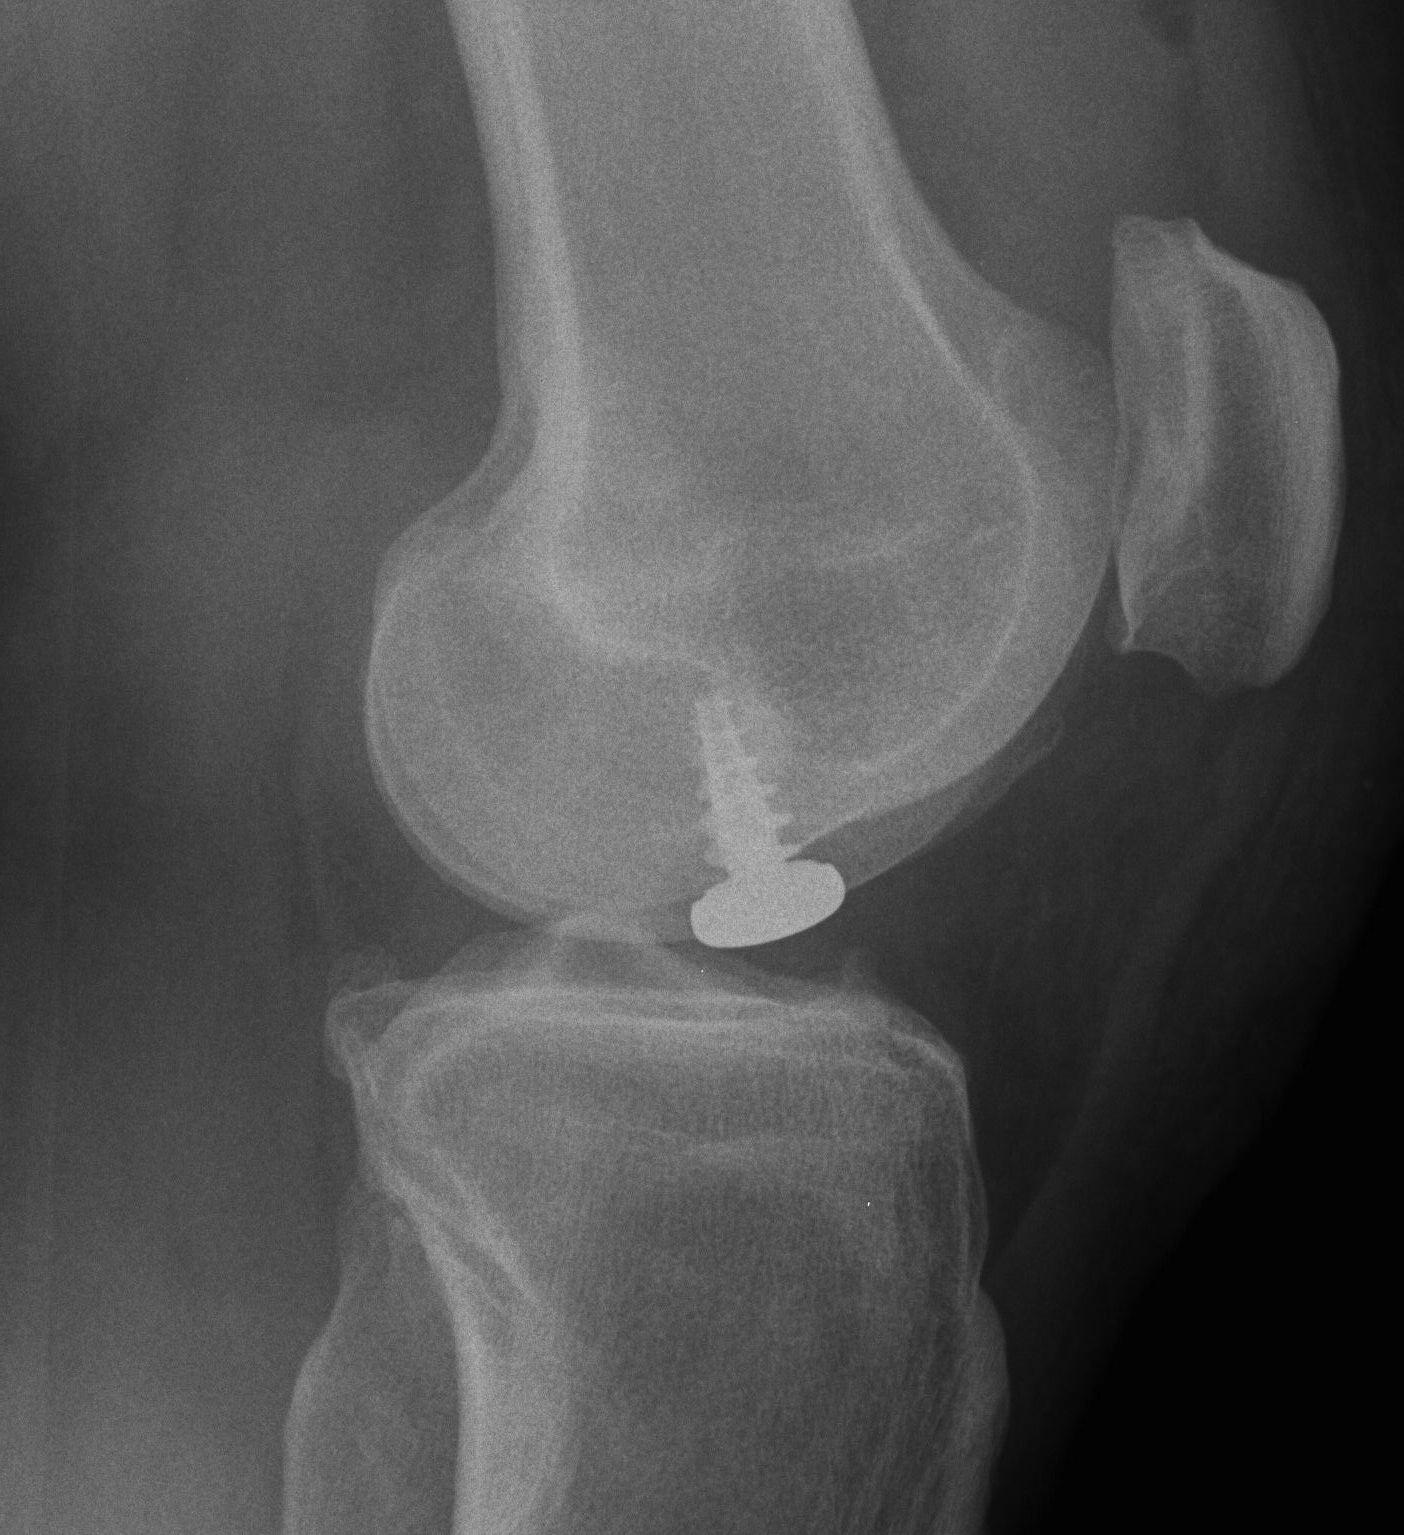

Osteochondral allograft

Principle

Indication

- very large, non contained defects

- previous failed cartilage procedures

Advantage

- restore anatomic contour

- nil donor site morbidity

- viable chondrocytes on fresh allograft < 30 days

Pre and post OCA with HTO

Use CT to get appropriate size graft

Match curvature of radius of donor site

Press fit